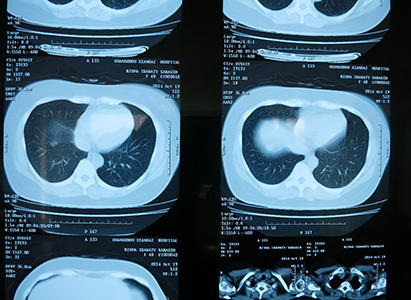

利斯马在广州现代肿瘤医院先后做了4次介入化疗,一次放疗和一次免疫治疗。由于这些治疗都是微创的,因此手术后她并没有什么不适的感觉。据她本人描述:做介入的医生很有经验,伤口很小,副作用也很少。她没有掉什么头发,没有呕吐,胃口也很好,甚至长胖了3公斤。利斯马对治疗效果也感到很满意。她说,入院诊断是子宫内膜癌术后复发,肝、肺转移,可是治疗后肝部肿瘤就消失了,仅在肺部还剩下一些残留的病灶。CT结果显示之前被肿瘤压迫变形的膀胱也恢复了正常,因此长期困扰她的腹痛也消失了,大便恢复了正常,失眠的症状也得到了改善。